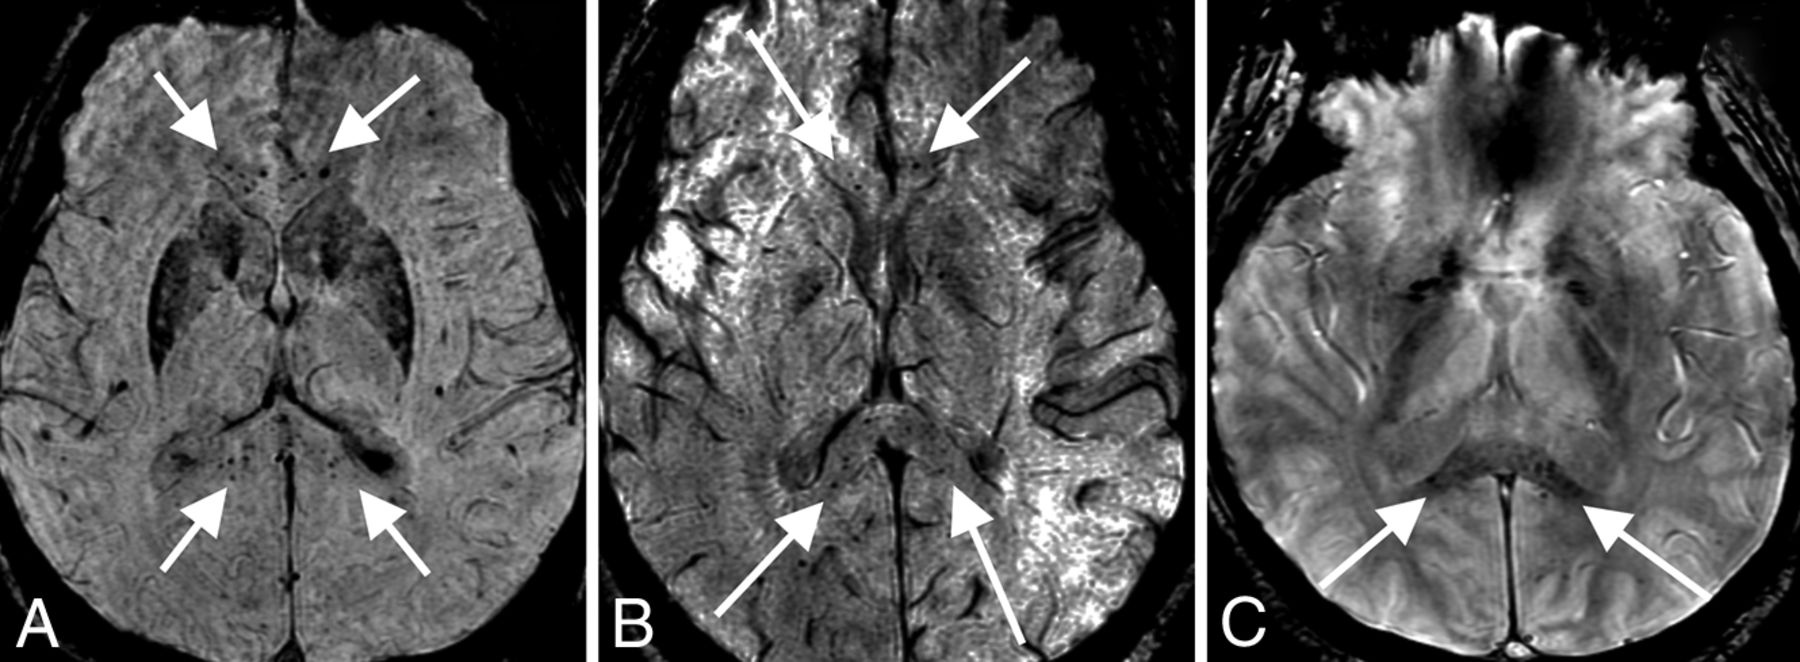

Given the prevalence of anosmia in patients with COVID-19,21⇓-23 our department added thin-section coronal T2 imaging through the olfactory bulbs to brain MRIs for all patients with COVID-19 in whom clinical status allowed the additional scan time. A total of 13 examinations (12 patients; mean age, 58 years; 6 women) included both diagnostic olfactory bulb sequences and high-resolution 3D-T2 FLAIR sequences; these studies were included in a separate systematic review (S.B. Strauss, unpublished data, May 2020). Briefly, no patient demonstrated changes in olfactory bulb volume. However, 4 of 12 patients demonstrated abnormally increased olfactory bulb signal on postcontrast T2 FLAIR, which may reflect intrinsic T2 prolongation or, potentially, contrast enhancement (Fig 5). No abnormalities were identified along the olfactory clefts within this cohort to correlate with findings reported in a prior case report of olfactory cleft obstruction in a patient with COVID-19 with anosmia.15 One of the 4 patients with olfactory bulb signal abnormality had documented anosmia, but for the other 3 patients, there was no clinical documentation addressing either the presence or absence of anosmia.

Olfactory neuritis. Six patients with COVID-19 with coronal T2-FLAIR postcontrast images. A 48-year-old woman (A) demonstrates hyperintense signal in the right (arrow) greater than left olfactory bulbs. A 52-year-old woman (B) and a 62-year-old man (C) demonstrate symmetric hyperintense signal in the olfactory bulbs (arrows). For comparison, 3 different patients (D–F) in our cohort with normal olfactory bulbs (arrows) are included.

We also found that 4 of our patients with COVID-19 had evidence of an olfactory neuritis, with hyperintensity of the olfactory bulb on postcontrast T2 FLAIR images, potentially a biomarker of disease and an imaging correlate of the anosmia commonly experienced by patients. Recently, it has been shown that sustentacular cells of the olfactory epithelium (technically part of the peripheral nervous system) express the angiotensin converting enzyme 2 (ACE2) receptor,36 providing a potential entry point to the CNS via synapses with the olfactory bulbs. Extension to the brain may occur via further trans-synaptic spread, as has been shown to occur in other coronaviruses.37 For example, transnasal exposure in mice to the related coronavirus SARS-CoV resulted in detection of the virus in regions with direct neuronal connection to the olfactory bulb: the piriform and infralimbic cortices, basal ganglia, and midbrain.38 Another coronavirus, Middle East respiratory syndrome coronavirus, has also been shown to invade the brain of mice when administered intranasally.39 Trans-synaptic spread may also allow coronaviruses to gain access to the CNS via other parts of the peripheral nervous system.37